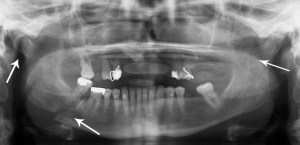

Symptomatic isthmic spondylolysis in the adolescent athlete — for many of us in the world of primary care sports medicine who have a large pediatric/adolescent patient base, this is one of the more common clinical entities we treat.

Recently published “On Line first” in CJSM is research coming from a Japanese center renowned for its work in this area: Low-intensity Pulsed Ultrasound (LIPUS)for Early-stage Lumbar Spondylolysis in Young Athletes.

The spring Journal Club commentary for the Clinical Journal of Sports Medicine will be a review of new research examining the effects of pulsed ultrasound for early-stage lumbar spondylolysis in young athletes. This is a retrospective case control therapeutic study with level three evidence. The specific aims of the study were 1) to determine differences in median time to return to previous sports activity with and without the use of low intensity pulses ultrasound (LIPUS); and 2) to determine if healing rates are improved with LIPUS. Read more of this post